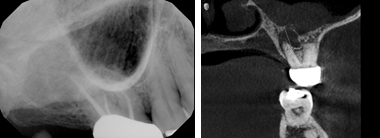

I also came across multiple referred patients with a history of sinus problems, who presented to our imaging center experiencing a toothache, and the 2D digital image that was taken at their dental home showed no obvious concerns. The 3D cone beam CT scan we took showed a defect in the bone and the infection draining into the sinus like the example pictured here.

Seeing the results of their images made me wonder; is the patient’s sinus infection caused by a nasal infection or a tooth infection draining into the sinus cavity? When a patient presents with a chief complaint regarding their gingiva, I assume a popcorn kernel could be lodged subgingivally or perhaps flossing trauma. Now I’m wondering, could the pain be bone loss occurring that is not yet viewable on a 2D digital image? What about our patients who present to their appointment with no chief complaints and their periodontal assessments and 2D digital images appear fine? Are those patients really within normal limits with no obvious concerns?